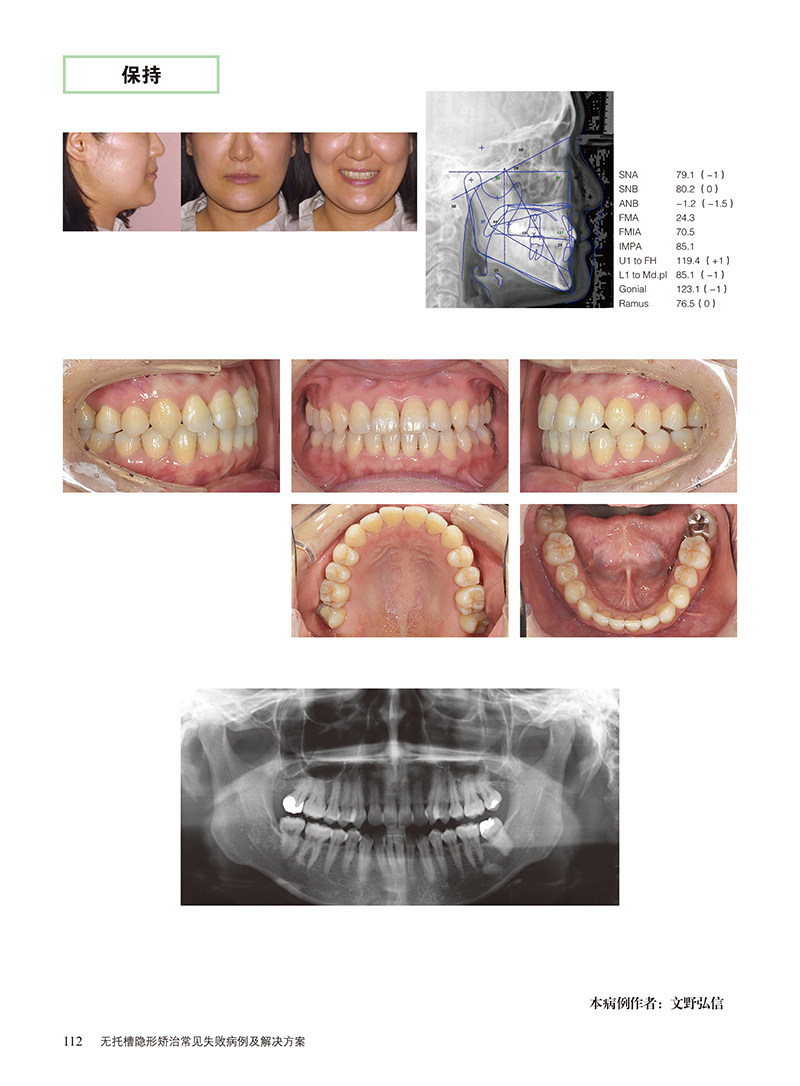

无托槽隐形矫正法与以往的矫正法有不同的特点,如果没有正确的知识和技能,会招致各种各样的麻烦和失败。本书整理了矫正失败的相关知识和经验,将失败的机制和有效的恢复方法系统化。通过找到失败的原因,在能够满足患者的要求的基础上进行适当的治疗。本书分享了31个失败的病例,介绍了矫正治疗中常见的疑点和难点,并提供了相应的解决方案。我们希望本书对广大读者的临床实践有所帮助,也希望最终诞生的这种应用计算机辅助技术的治疗方法能够朝着正确的方向发展。